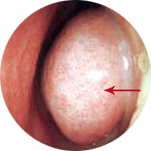

ÄÚ ³»½Ã°æ ¼Ò°ß

img

ºñÈļº ºñ¿°